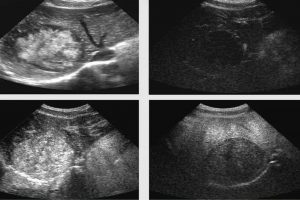

Diplomado en Ultrasonografía Médica

El programa fue diseñado para llevar de la mano al participante y ofrecerle herramientas que le permitan hacer una evaluación radiológica atinada, lo cual lo llevará a un diagnóstico que por ende arrojará el tratamiento idóneo. El énfasis se ha dado en la metodología diagnóstica, que es por inducción, así como el manejo del paciente, para crear una conciencia responsable y humana entre los que se dedican o quieren iniciarse en la práctica de la ultrasonografía. Dado a que existe una aplastante demanda de estudios de ultrasonido ante el insuficiente número de médicos radiólogos certificados, además de que el servicio de rayos x en México ha sufrido de ineficiencia en la aplicación del estudio y elaboración diagnóstica de la patología, la labor de este curso es formar de manera profesional a los médicos para que cubran y aminore en gran medida este problema que habita en el sector de salud.